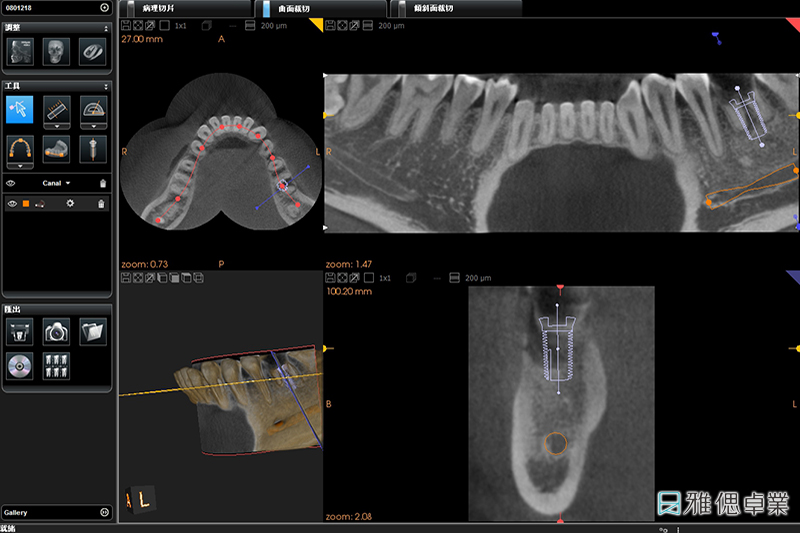

什麼是3D數位植牙?

數位植牙是藉由影像導引(Imaging Guide)的技術保留手術導引(Surgical Guide)與電腦導航(Navigation)技術的優點,讓牙醫師在進行植牙手術時,清楚知道鑽孔的軸向與位置,即時改變或修正植牙手術計劃。

在植牙療程的過程中,專業醫師會透過「植牙規劃軟體」找出合適的植體大小及植入位置、角度與深度,再為患者設計專屬「手術引導板」,將手術引導板安裝在於患者的缺牙位置,定位適當的角度、位置與深度,快速完成高效能數位植牙療程、大幅提升植牙治療的舒適體驗!

植牙手術導引板設計過程